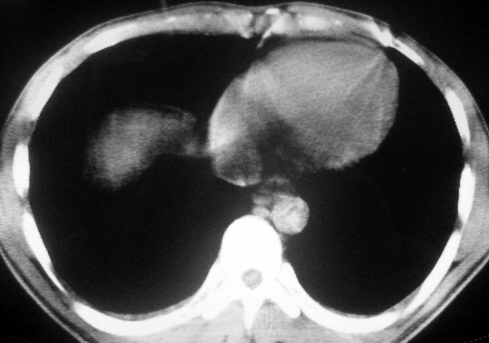

男,36岁,一月前醉酒淋雨后发热咳嗽,气短进行性加重.

抗生素治疗无效,痰检(一).

影像诊断:结核? 还有其他考虑吗?

双肺内中部见略不对称性蝶翼状高密度区,边界不清,部分呈磨玻璃样密度,并可见含气支气管征。肺门、纵隔内未见肿大淋巴结影。无胸腔积液。

考虑:1、肺炎,建议进一步查冷凝集试验除外支原体肺炎;

2、不除外霉菌感染。

双肺斑片状密度均匀病灶,边界模糊可见充气支气管征,上野多于下野,不支持结核,1肺内感染,2查肾功,中心型肺水肿待除外.

双肺中上野对称分布蝶翼样不均匀密度增高影,有支气管充气征,纵隔未见肿大淋巴结,发病突然,抗炎治疗无效,还是要考虑结核。

还是考虑肺水肿!蝶翼征.肺门增大,肺血管影增粗,!!病变累及中内带为主!要排外支原体感染.

支持: 双肺内中部见略不对称性蝶翼状高密度区,边界不清,部分呈磨玻璃样密度,并可见含气支气管征。肺门、纵隔内未见肿大淋巴结影。无胸腔积液。